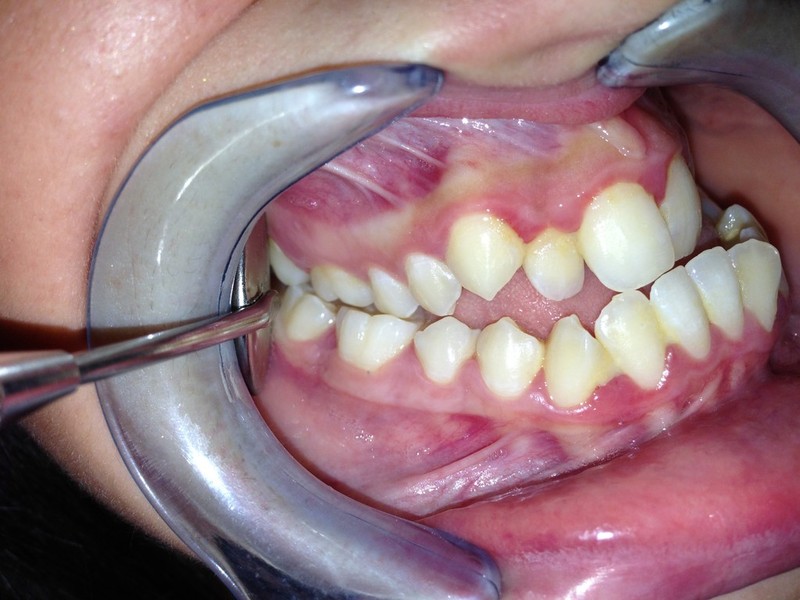

Paziente candidato a intervento di chirurgia Ortognatica

I risultati Arrivano e si vedono.

Uno dei nostri ultimi cambiamenti radicali.Il tuo sorriso può essere più vicino di quello che immagini